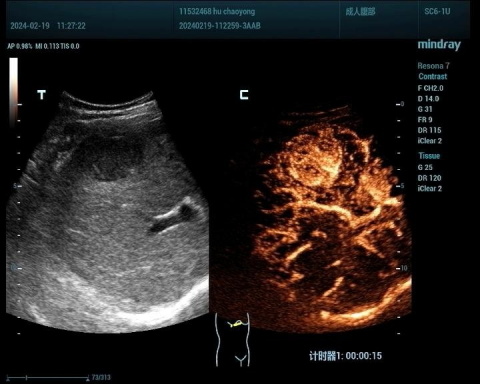

1、肝脏占位性病变:

肝脏肿瘤分为良性和恶性,其中血管瘤是最常见的肝脏良性肿瘤,肝癌是最常见的恶性肿瘤。肝脏肿瘤超声影像诊断方面主要有肿瘤病灶的检出、对已检测肿瘤的定性诊断、肝局灶性病灶中肿瘤与非肿瘤病变的鉴别。超声造影对肝脏肿瘤的鉴别诊断主要是通过增强和动态增强方式观察肿瘤。

肝癌病例1

肝癌病例2

肝血管瘤